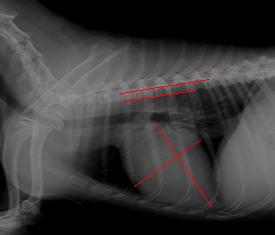

No, en la radiografía pueden verse diferentes tejidos con distintas densidades, en este caso, una placa de tórax nos deja ver la silueta del corazón, valorar su tamaño e incluso podremos ver el diámetro de ciertos vasos sanguíneos importantes, así como el estado de los pulmones (que pueden contener líquido a causa de la insuficiencia cardíaca secundaria a esta enfermedad, llamado edema pulmonar) y otras estructuras como la tráquea.